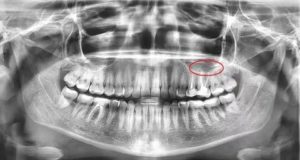

Только на рентген снимке или на экране компьютера при томографии можно обнаружить проблему.

- рентген снимок, который показывает не только наличие тела, но и пневматизацию (наличие воздуха);

Для многих людей может показаться невероятным факт нахождения в гайморовых пазухах инородного тела. Однако врачебная практика показывает частые случаи этого явления. Особенно стоит насторожиться людям, которые долго лечат гайморит. Следует провести диагностику и проверить наличие постороннего тела в гайморовых пазухах с помощью компьютерной томографии или простого рентгеновского снимка.

Наверняка каждый человек лечил зубы, и часто лечение сопровождается пломбировкой каналов зуба. Дело в том, что корни верхних зубов особенно 5 и 6-го часто вдаются в верхнечелюстную пазуху и прикрыты со стороны пазухи только слизистой оболочкой.

Таким образом, стоматолог, совершенно без злого умысла, проводя работу над корнем зуба, может проткнуть ее верхушку и протолкнуть пломбировочный материал в пазуху. Более того, иногда в пазуху может попасть даже фрагмент самого корня зуба или корень полностью. Вот тут и начинается самое интересное.